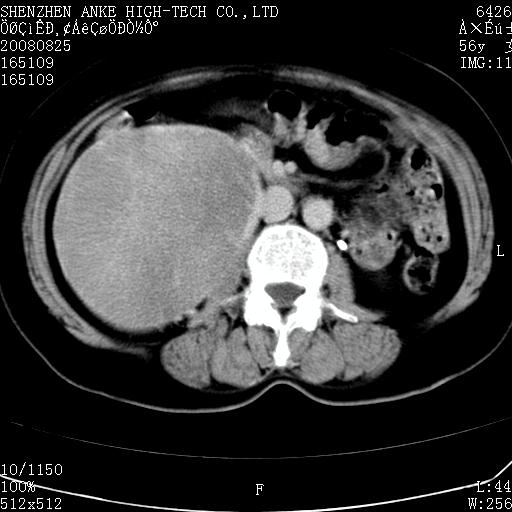

患者,女性,56岁,腰痛3年,查:右腹部约8x10cm肿块,固定,无压痛;8月23日在外院做了平扫,发现右肾巨大肿块(外院具体诊断不祥);今天在我院做了静脉肾盂造影,示:右肾明显增大,分泌功能明显减弱。

1)考虑右肾癌并右肾静脉瘤栓形成。2)脂肪肝。